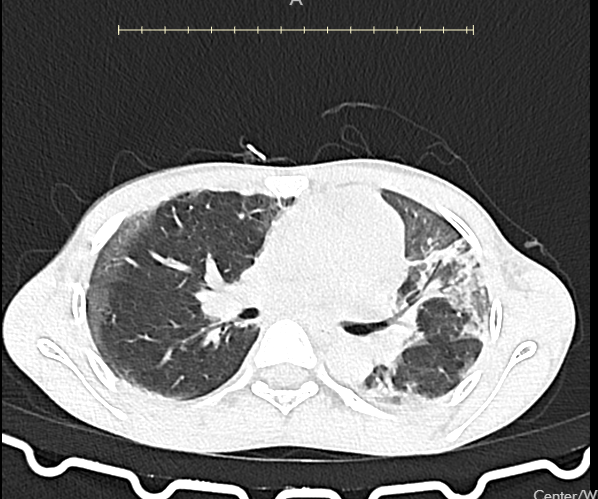

Both of them were rushed to our ward. Both of them had CT scans that showed the extent of their lung damage. Both of them fought, and we fought with them. But in cases like these, our fight feels so unfair—because the poison is almost always stronger than medicine.

Child A

Child B